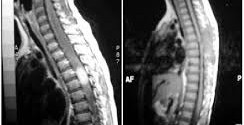

PARAPLEJIA ESPASTICA HEREDITARIA

La paraplejía espástica hereditaria es un grupo de enfermedades degenerativas genéticas de la médula espinal. Caracterizado por debilidad progresiva es decir, paraplejía o paraparesia y rigidez, es decir, espasticidad con un excesivo tono muscular o hipertonía, o con sobre actividad muscular con aumento de la resistencia al estiramiento de los músculos de las piernas. Si fuese su deseo le podemos …